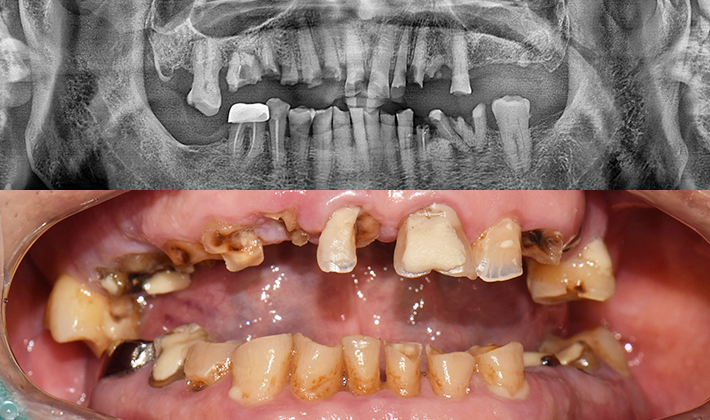

5060 시니어 임플란트

건강하고 오래가는 시니어 임플란트,

치료 사례부터 남다릅니다.

before

after

※ 위 임상사진은 동일조건으로 촬영되었으며, 사진에 대한 별도의 조작이 처리되지 않았습니다.

※ 위 임상사진 및 포트레이트는 환자와의 포괄적인 초상권 계약 이후 사용하고 있습니다.

※ 수술 및 치료과정에서 부작용이 발생할 수 있으므로 충분한 상담과 신중한 판단이 요구됩니다.

실제 치료 사례

수많은 환자들이 고민 끝에 선택한 치료,

그리고 그 후의 놀라운 변화

- ※ 위 임상사진은 365서울원탑치과에서 진료를 시작하고 마친 동일한 환자의 사진입니다.

- ※ 위 임상사진은 동일한 장소에서 동일한 조건으로 촬영되었으며, 사진에 대한 별도의 조작이 처리되지 않았습니다.

- ※ 수술 및 치료 과정에서 부작용이 발생할 수 있으므로 의료진과의 충분한 상담과 신중한 판단이 요구됩니다.